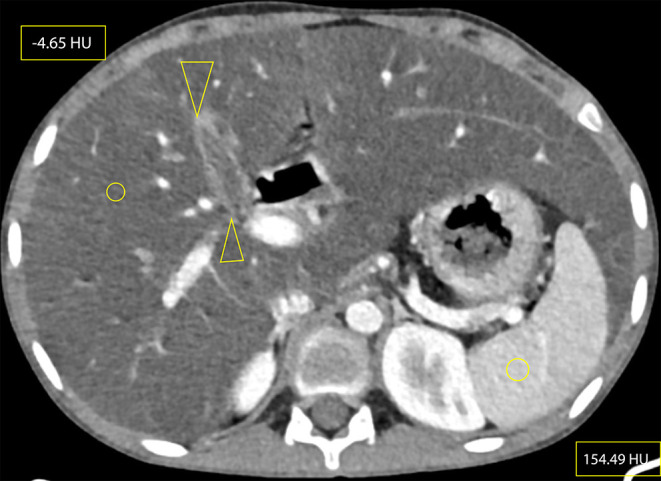

囊性纤维化(CF)是一种多系统疾病,是由于第 7 号染色体上的 CF 跨膜传导调节器(CFTR)基因突变导致的常染色体隐性先天性遗传。由于该病被认为是高加索儿科人群的疾病,或者由于缺乏认识,像我国这样的发展中国家很少考虑该病。本病例报告是埃塞俄比亚(也可能是东非)报告的首例囊性纤维化病例,患者是一名 17 岁女性,在对其腹部和胸部进行 CT 扫描后确诊患有该病。由于她长期咳嗽,最初被误诊为肺结核(TB)并接受治疗。也许是由于流行病学证据,在埃塞俄比亚,几乎所有慢性咳嗽伴有肺实质纤维支气管扩张病变的病例都被顽固地归咎于肺结核(TB)。一旦对这些病人做出结核病诊断,他们的诊断就会陷入结核病再感染、复发或耐药的怪圈,随后又要接受多个阶段的抗霉菌药物治疗。这可能会导致危险的影响,包括不必要的长期抗霉菌治疗、产生耐药性的可能性以及与管理不当有关的患者发病率。该患者的胸部和腹部 CT 结果,包括支气管扩张、肝脂肪变性、胰腺脂肪瘤、微小胆囊和近端结肠壁增厚,导致了 CF 的诊断。这篇文章介绍了该地区第一例有记录的 CF 病例,旨在提醒临床医生和放射科医生也要考虑像 CF 这样可能 "罕见 "的疾病,而不是把每一次慢性咳嗽都归咎于肺结核,并强调了腹部 CT 特征在 CF 诊断中的重要性。

Cystic fibrosis (CF) is a multisystem disorder that occurs as a result of autosomal recessive congenital transmission of CF transmembrane conductance regulator (CFTR) gene mutation on chromosome 7. Because it is considered a disease of the Caucasian pediatric population or due to lack of awareness, it is rarely considered in developing countries like ours. This case report presents the first case of cystic fibrosis ever reported in Ethiopia and possibly East Africa, that of a 17-year-old female diagnosed with the disease following a CT scan of her abdomen and chest. She was initially misdiagnosed and treated for tuberculosis (TB) as she was a chronic cougher. Perhaps due to epidemiological evidence, there is an obstinate tendency of blaming tuberculosis (TB) for almost every case of chronic cough with fibro-bronchiectatic lung parenchymal changes in Ethiopia. Once a diagnosis of TB is posted on such patients, their diagnosis remains in the circle of TB reinfection, relapse or resistance, followed by multiple phases of anti-mycobacterial drugs. This could lead to hazardous implications, including unnecessary prolonged anti-mycobacterial treatments, possibility of developing drug resistance, and mismanagement-related patient morbidity. This patient's chest and abdominal CT findings, including bronchiectasis, hepatic steatosis, pancreatic lipomatosis, micro-gallbladder and proximal colonic wall thickening, led to the diagnosis of CF. This article, presenting the first documented case of CF in the region, is meant to be a helpful reminder for clinicians and radiologists to also consider presumably "rare" illnesses like CF rather than blaming TB for every chronic cough and highlights the importance of abdominal CT features in the diagnosis of CF.